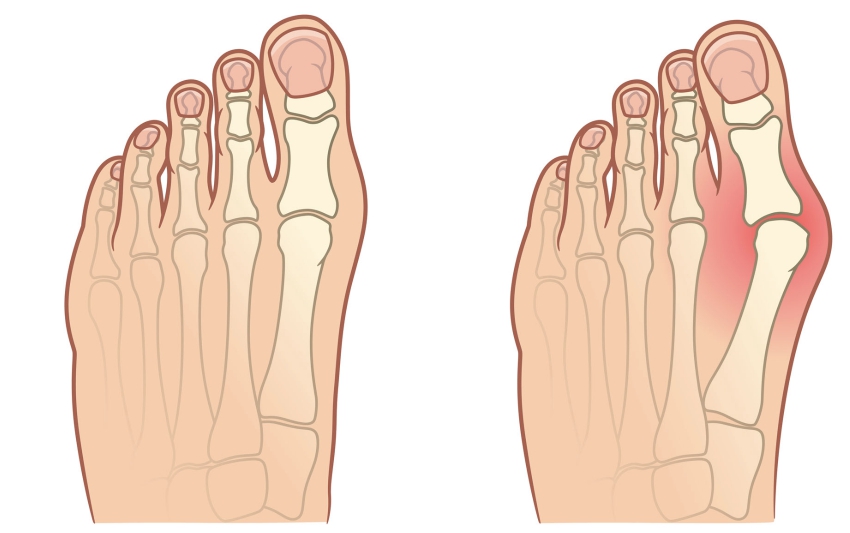

La articulación y la columna se desgastan con el paso de los años, pero si también se rompen por el sobrepeso, el trabajo físico extenuante, el transporte de objetos pesados, el exceso de deporte, las lesiones y los hematomas. El líquido sinovial y el cartílago han sido destruidos. Las juntas suenan como un tamiz sin lubricar: empieza a desgastarse y a degradarse constantemente. Con el tiempo, comienza a sentirse rígido y con un dolor insoportable que le impide moverse con normalidad. Si desarrollan inflamación y degeneración grave.

Desafortunadamente, las células del cartílago y del líquido sinovial no tienen la capacidad de curarse por sí mismas. Esto significa que, a diferencia de otras células del cuerpo humano, no podemos volver a estar sanos. Por eso las articulaciones y la columna empeoran día a día. Eso sí, no cambies la caminata y aprovecha las actividades diarias para proteger tus articulaciones y columna. Sería absurdo.

La fórmula única de Arthrozax actúa desde el interior del cuerpo, desactivando el dolor a nivel celular y permitiéndote seguir con tu vida sin molestias. Gracias a sus propiedades estimula la nutrición celular, lo que restablece los procesos regenerativos en un 300%. Al mismo tiempo, los ingredientes naturales inician los procesos de regeneración automática del cartílago y del líquido sinovial. El uso diario de las crema Arthrozax es suficiente para que el proceso de regeneración ocurra de forma continua las 24 horas del día. Haz lo que haces siempre y tus articulaciones y columna se rejuvenecerán y recuperarán la movilidad. De esta forma, la degeneración y el dolor desaparecen para siempre en 30 días. ¡Sin efectos secundarios!

ANTES

Articulación destruida y afectada por degeneración y dolor

DESPUÉS

Articulación regenerada: 100% sana y sin dolor